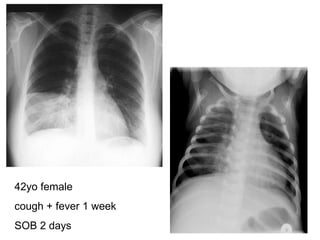

42yo female cough + fever 1 week SOB 2 days

CXR- Pneumonia Describe? Consolidation of R middle lobe Dx? Lobar pneumonia of R middle lobe 2 etiological agents? Strep. Pneumoniae Hemophilus Influenzae * Staphy. Aureus (bilat cavitating bronchopneumonia)

CXR- Pneumonia Describe?Consolidation of R middle lobe Dx? Lobar pneumonia of R middle lobe 2 etiological agents? Strep. Pneumoniae Hemophilus Influenzae * Staphy. Aureus (bilat cavitating bronchopneumonia)